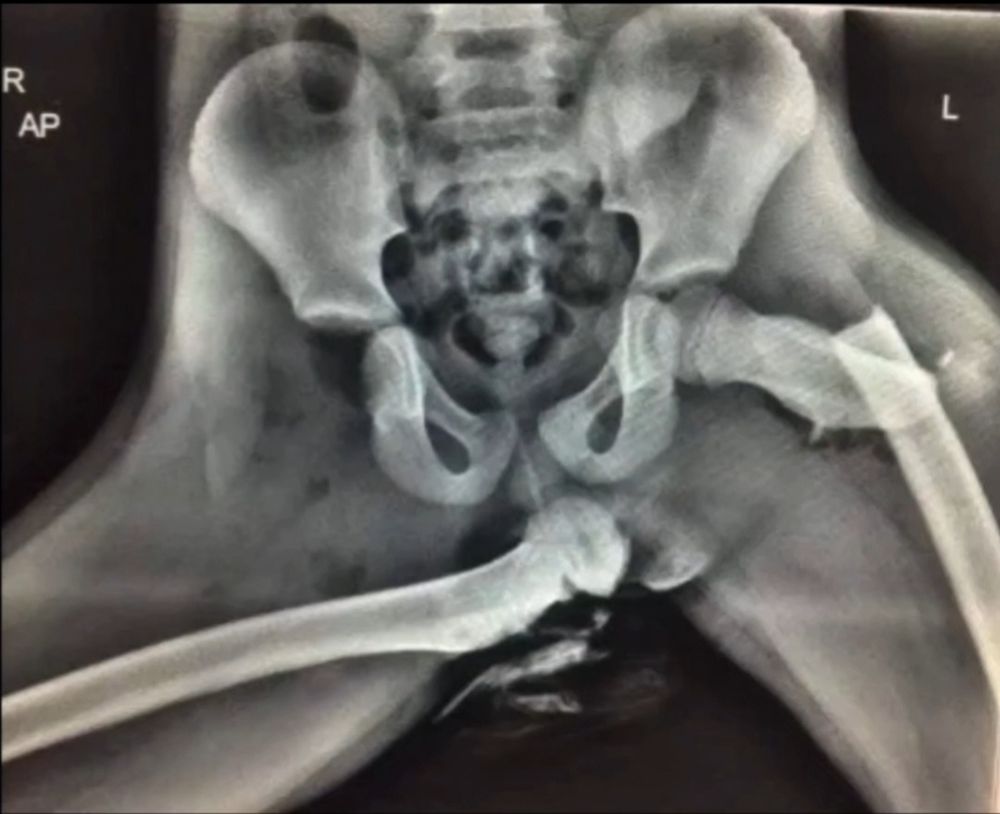

A young woman who has been injured in motor accidents.

Bilateral femur fracture and severe dislocation.

#Accident #vehicle #Motor #trauma #injury